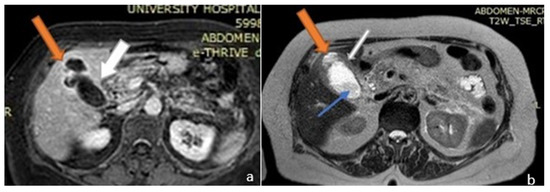

2.1. Case 1